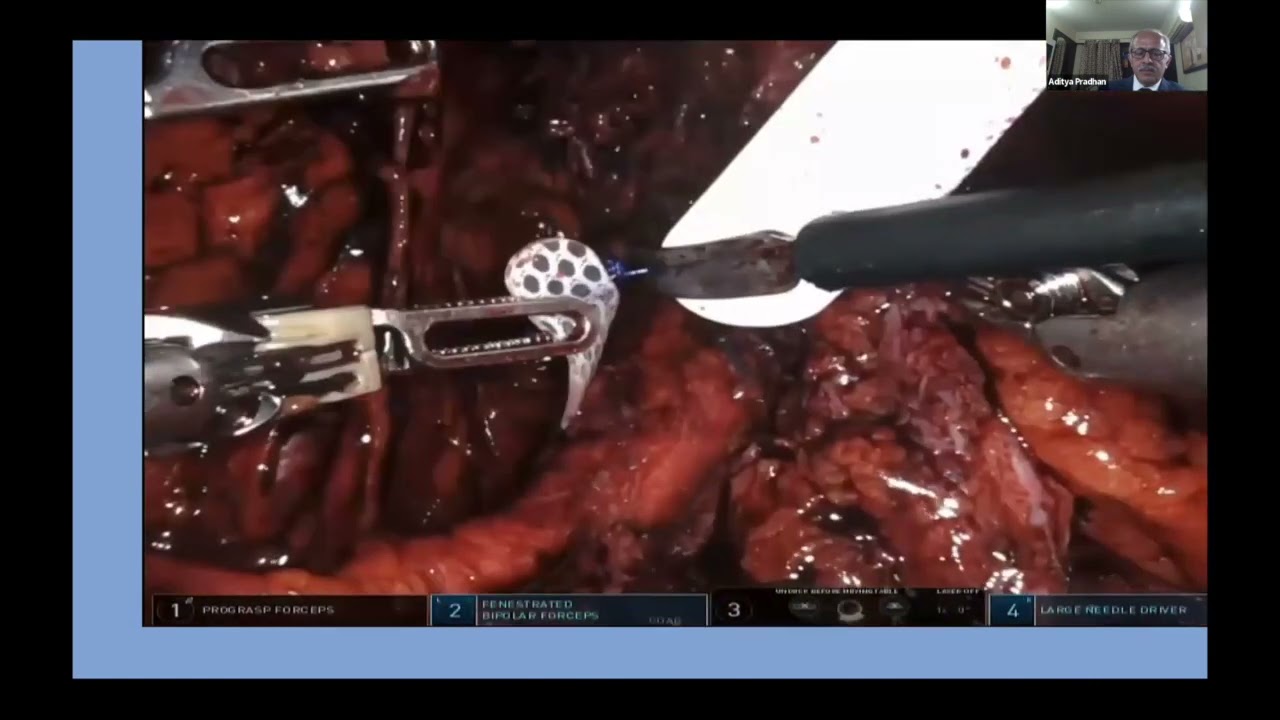

Bladder Neck Placement of AUS in Extrophy-Episadias- A Case Report- Dr. Aditya Pradhan

Masterclass, Robotics, Surgeon, Urology ';